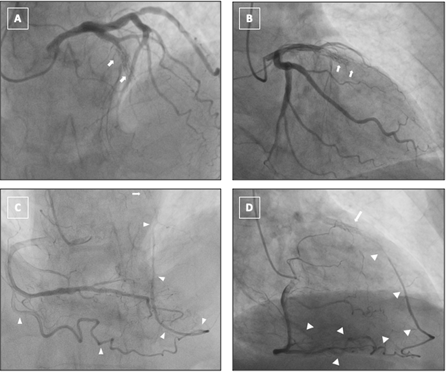

Diagnostic CAG revealed a chronic total occlusion (CTO) within the previously stented segment of the mid-LAD (Figure A and B; Videos 1 and 2). The lesion was heavily calcified, longer than 20 mm, and exhibited a tapered proximal cap. Importantly, no antegrade opacification of the distal LAD was observed. A single epicardial collateral channel originating from the acute marginal (AM) branch of the right coronary artery (RCA) was seen supplying the LAD territory (Figure C and D; Videos 3 and 4). No septal or secondary collateral pathways were visualized.